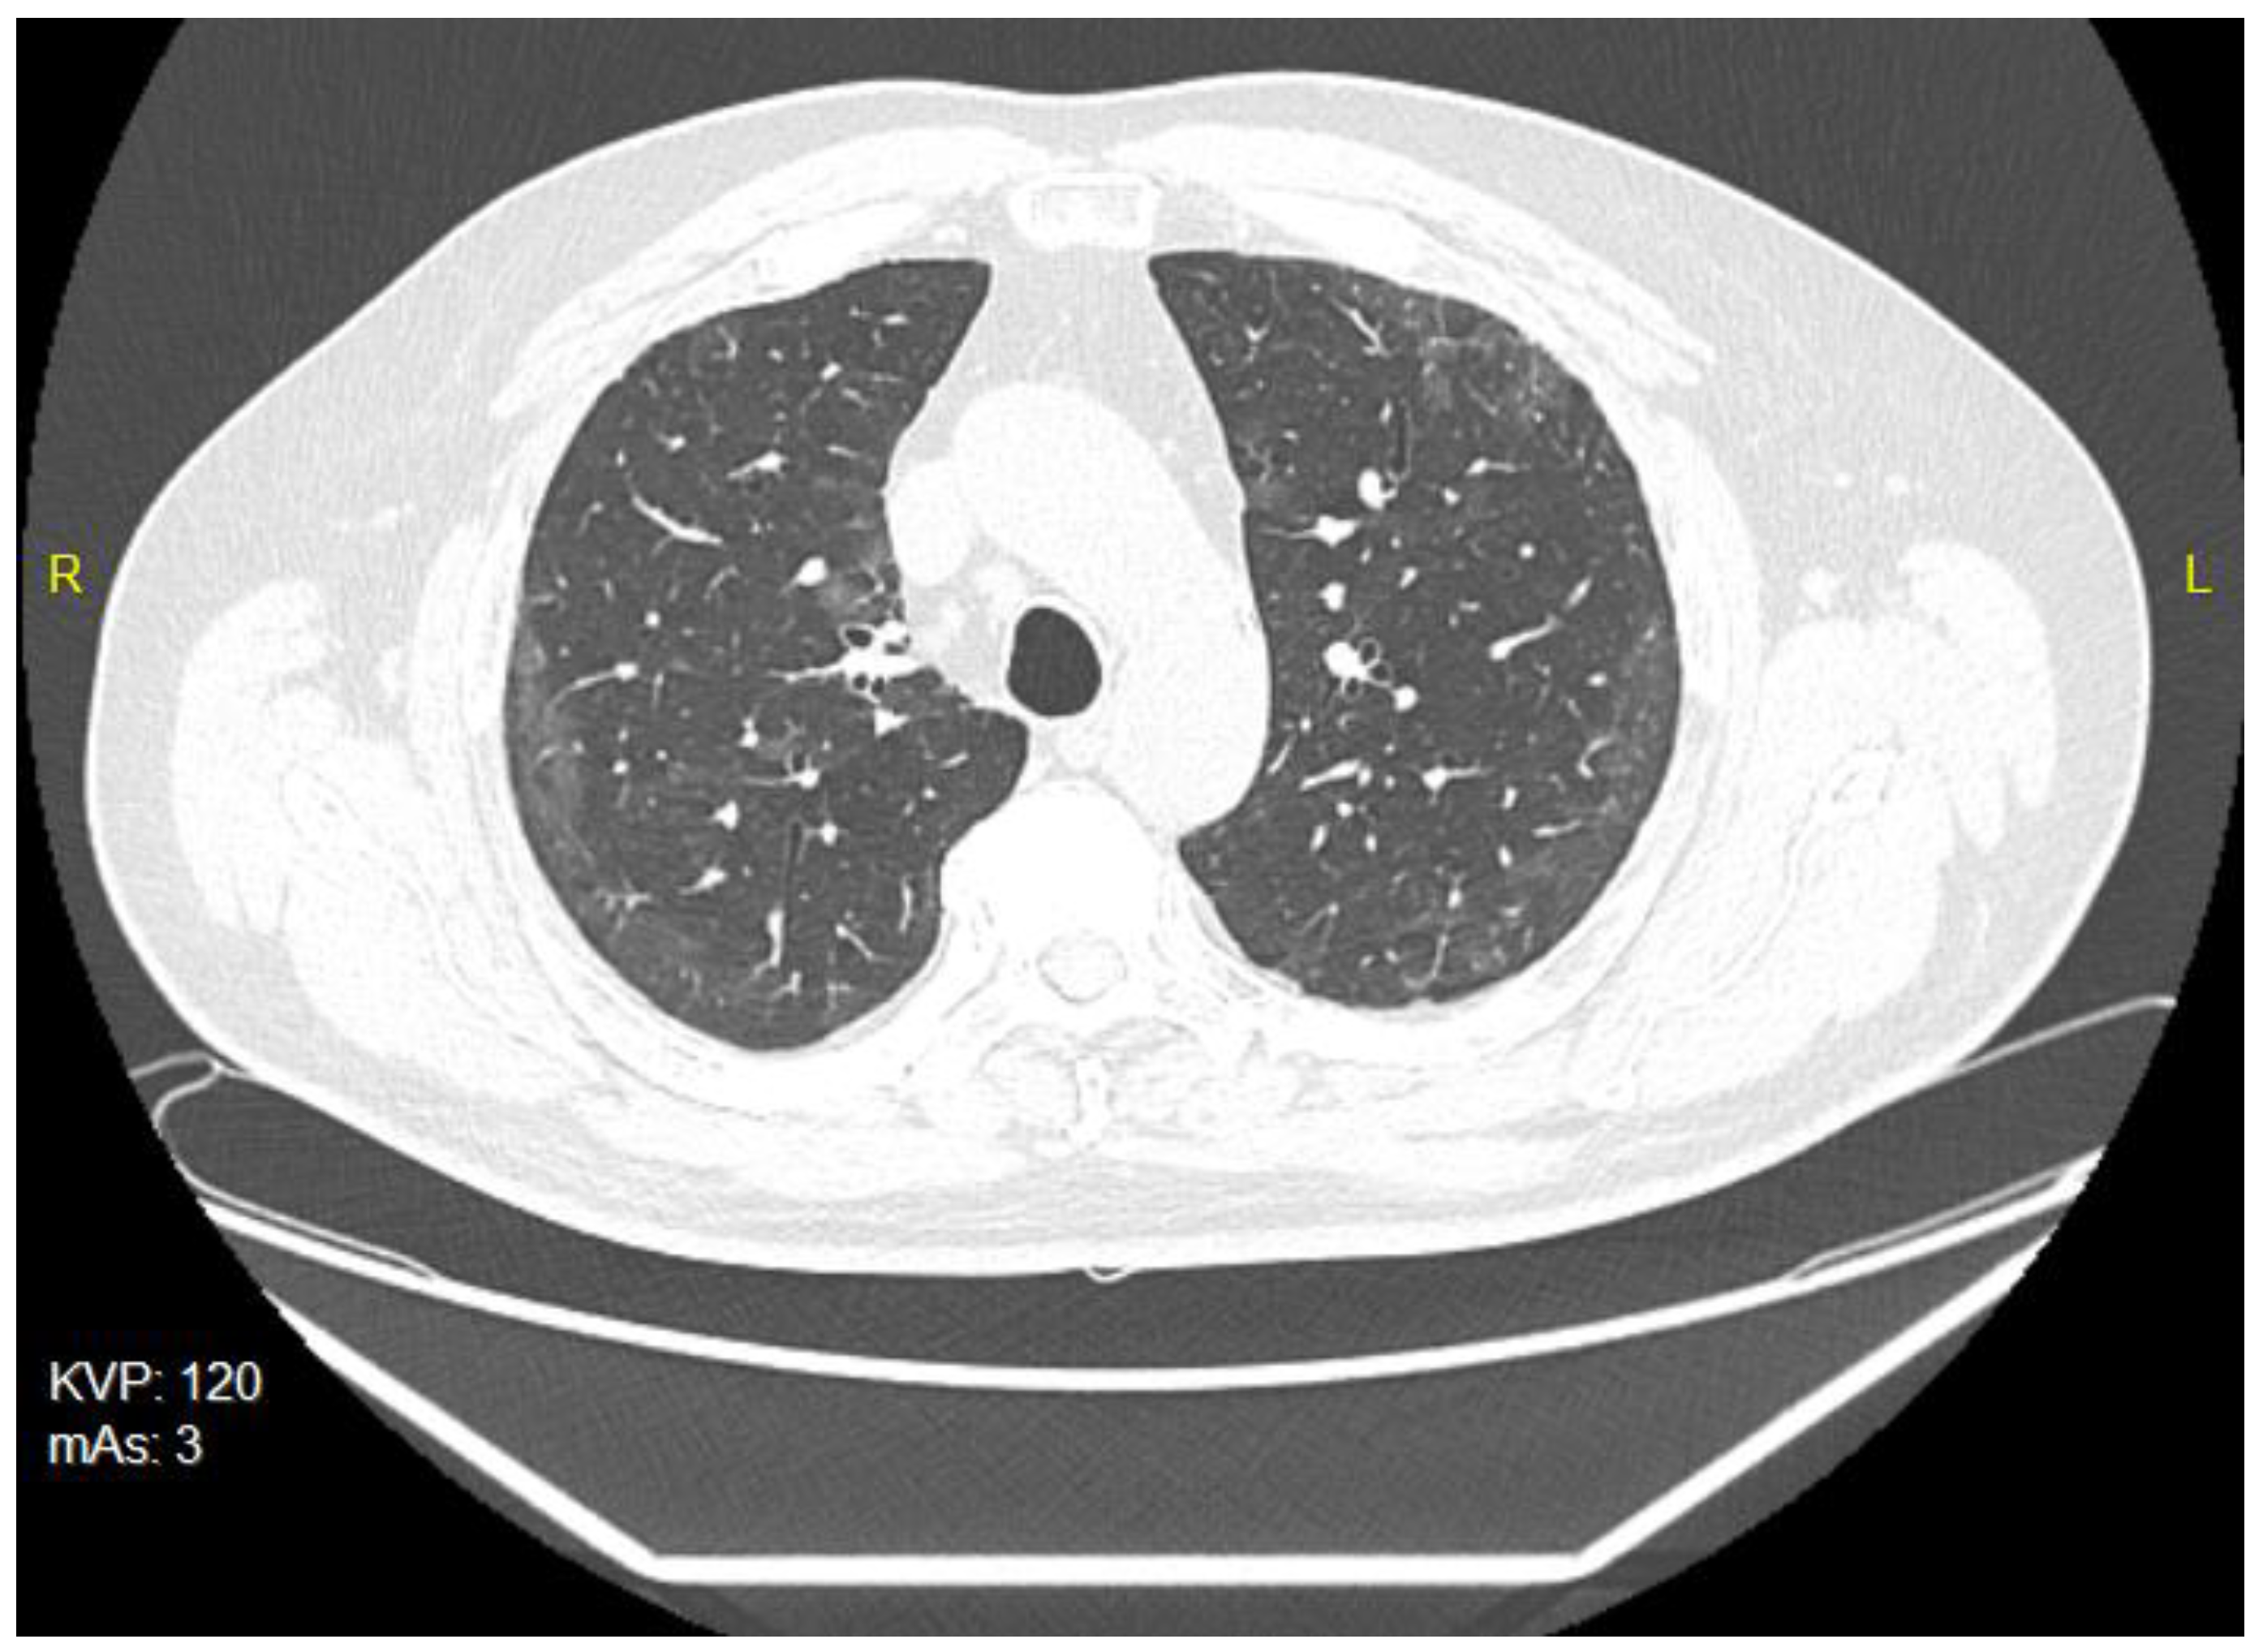

The patient was treated on an outpatient basis, as he complained of cough, breathlessness and fatigue. He was treated with azithromycin administered in a dose of 500 mg for 3 days. The chest X-rays revealed streaky parenchymal densities. The chest CT of 5 February 2021 showed areas of reduced transparency with mainly peripheral distribution, creating locally poorly saturated interstitial ground-glass opacities. There were also visible streaky parabronchial opacities—cicatricial—residual or post-inflammatory, especially at the base of lower lobes of both lungs, and traction of the nearby bronchi, showing slight signs of bronchiectasis (Figure 3). The Aidmed-assisted monitoring was conducted from 10 August 2021 to 23 August 2021. The total duration of the study was 31 h 38 min. The following events were recorded: 93 episodes of Tachypnea (over 25 breaths/min.), 242 episodes of decreased saturation (below 90%) and 716 episodes of tachycardia (over 100 beats/min.) (Table 3). Moreover, on 20 August 2021, during the night monitoring lasting 6 h 28 min, the patient experienced 194 episodes of sleep apnea, mainly in the supine position, and 4 episodes of shallow breathing (Figure 4). The average duration of an apneic episode was 24.02 s, while the longest one went on for 101 s. The AHI (number of apneic and dyspneic episodes) reached 29.98, which corresponds to moderately severe apnea. The lowest recorded blood oxygenation value was 89%, while the total time of saturation below 90% was 52 min.

Figure 3.

The chest CT scan of 5 February 2021—bilateral ground-glass opacities.